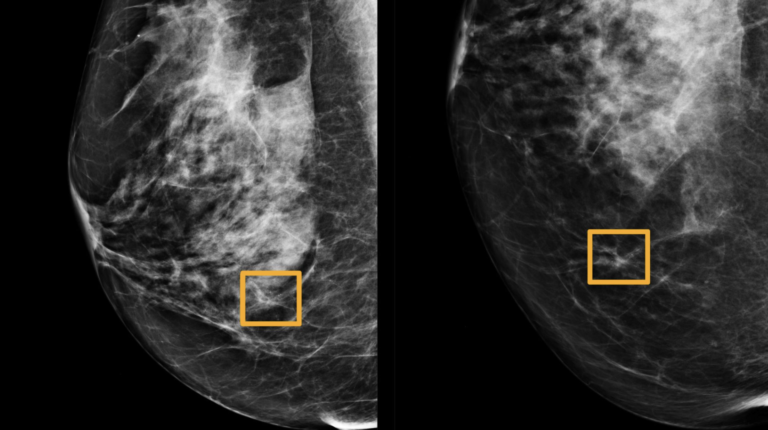

An artificial intelligence program was developed by Google that outperforms clinical specialists in detecting breast cancer in…